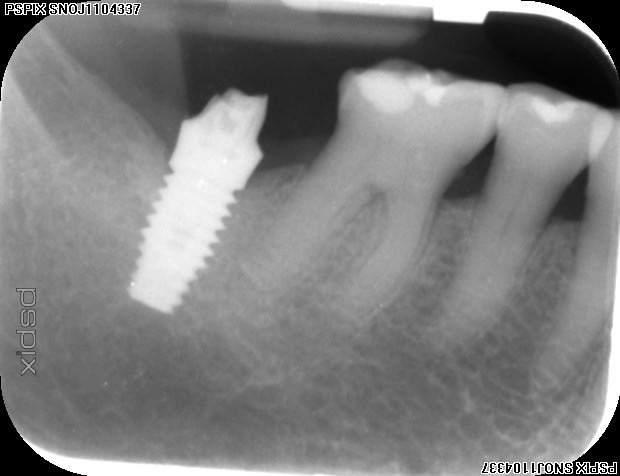

Pourriez vous me donner un coup de main pour identifier cet implant s'il vous plait?

Il a été posé il y a 8 ans et il faut que je change le pilier.

Je pense que c'est du biomet 3i mais rien de sur, je n'en pose pas.

dommage on voit pas bien la connexion par manque de contraste....mais amha oui çà ressemble bien à du Biomet 3i...